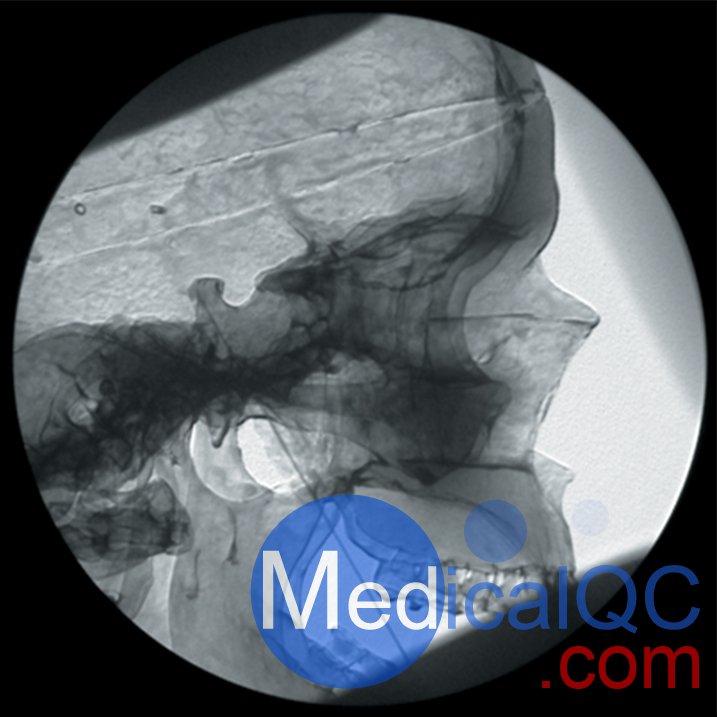

AR351脊椎穿刺模體,Adam,Rouilly脊椎穿刺模體是區(qū)域麻醉模擬人體模型,由曼徹斯特和索爾福德疼痛中心的顧問麻醉師設(shè)計的,用于培訓(xùn)麻醉師正確放置神經(jīng)塊中的針頭以進(jìn)行疼痛處理。

人體模型由特殊涂層的塑料人體骨骼組成,頭部覆蓋著人造皮膚,軀干覆蓋著織物,受訓(xùn)人員可以在其上練習(xí)在X射線圖像增強器控制下放置針頭

人體模型的X射線密度低,因此減少了模擬程序中使用的輻射劑量

The Regional Anaesthesia Simulation Manikin has been designed by a Consultant Anaesthetist at the Manchester and Salford Pain Centre for training anaesthetists in correct needle placement in Nerve Blocks for pain management.

Accurate needle placement is required to guarantee the efficacy of many diagnostic pain clinic blocks and is mandatory when neurolytic solutions are used. Radiological screening to confirm needle placement should be routine and training for this needs to be practical